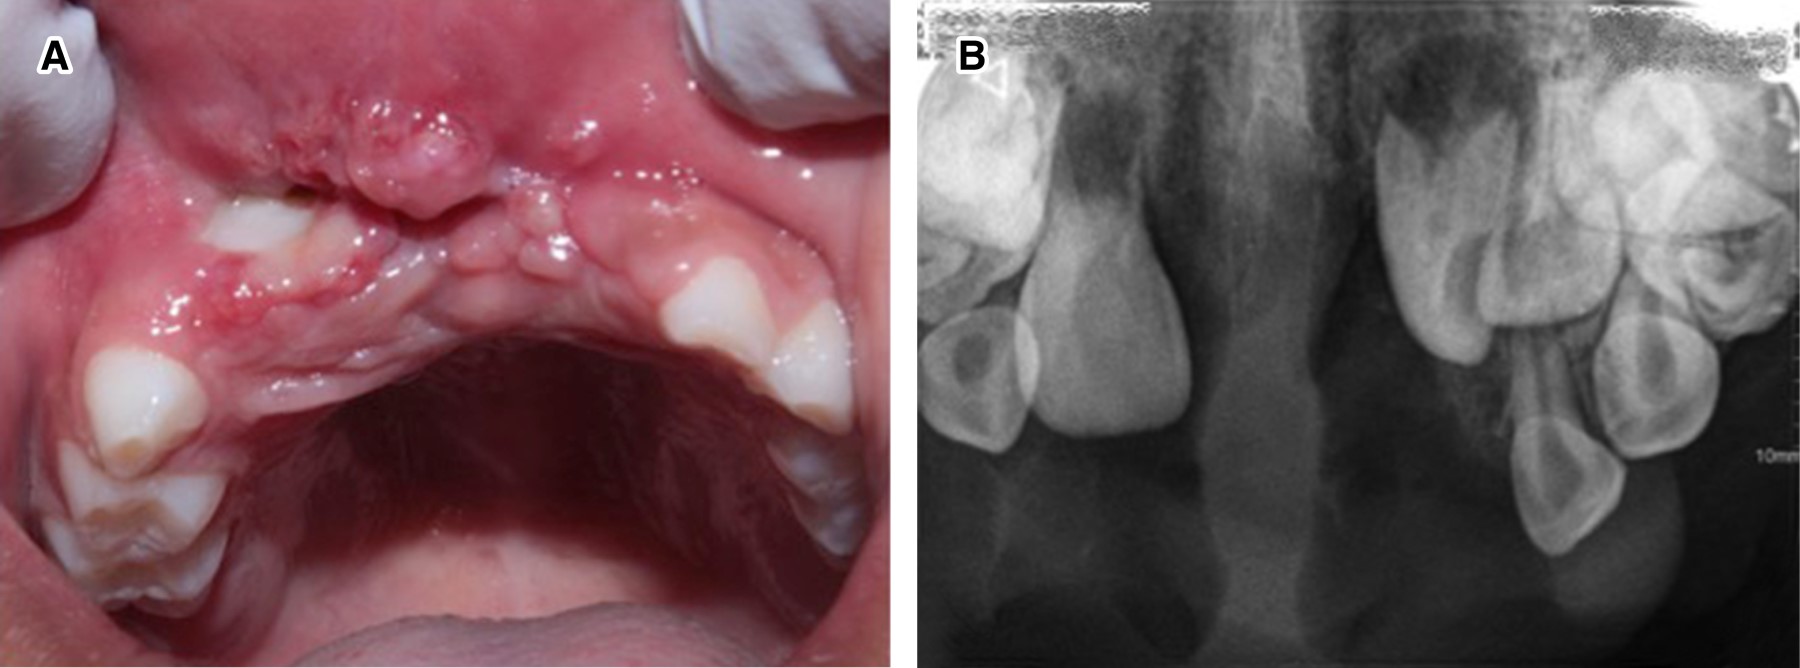

Se descartó una lesión quística y tras la evaluación multidisciplinaria se realizó exéresis quirúrgica bajo anestesia general (Figura 5). Se infiltró anestésico local (lidocaína/epinefrina), seguido de la incisión con bisturí y electrobisturí para su posterior remoción (Figura 6). Con ayuda de una legra se obtuvieron múltiples fragmentos firmes de color amarillo (de 25.0 × 25.0 × 10.0 mm la de mayor tamaño, y menor de 5.0 × 5.0 × 4.0 mm) y se suturó. Se determinó histopatológicamente la presencia de células gigantes multinucleadas (Figura 7), lo que permitió confirmar que se trató de un granuloma central de células gigantes. Se retiraron los puntos 10 días después de la intervención.

Figura 5

Figura 6